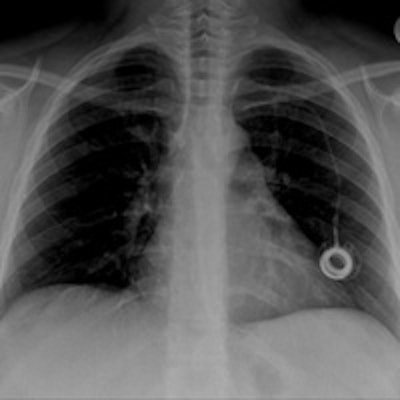

Case report: Retrieval of portacath fragment

Portacaths are commonly indicated for long-term administration of parenteral medications. This case report details the successful interventional retrieval of a fractured portacath fragment with cardiac migration. This is rather an unusual complication that, at times, can be life-threatening.